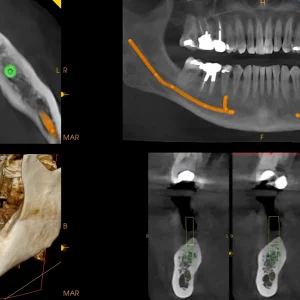

JEDINSTVENA CS MAR TEHNOLOGIJA

Ekskluzivni CS MAR tehnologija s alatom za usporedbu u stvarnom vremenu drastično smanjuje metalne artefakte, podržava dijagnostičku potvrdu i smanjuje rizik od pogrešnog tumačenja.